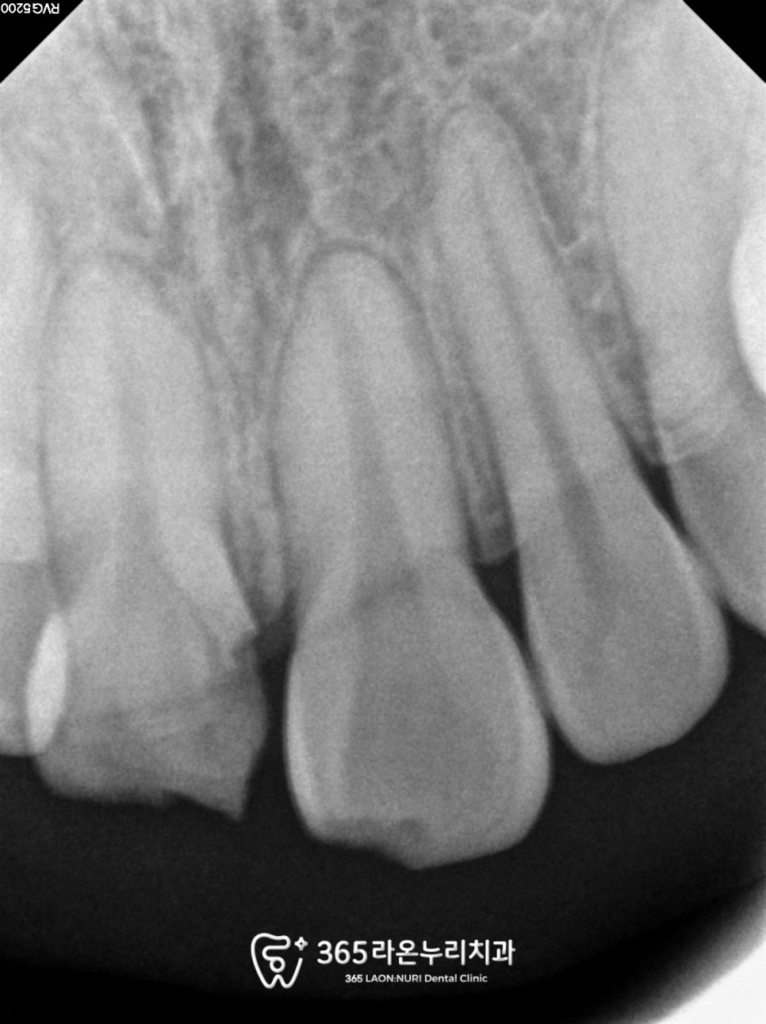

신경에 문제가 있나

오산대역 치과 에서

치근단 사진을 확인해 보았습니다.

다행히 치근(이의 뿌리)에는 파손이 없었으나,

치관 표면에서 신경이 드러난 상태였습니다.

이는 통증과 감염의 위험을 유발할 수 있어

이런 경우 빠른 처치가 필요합니다.